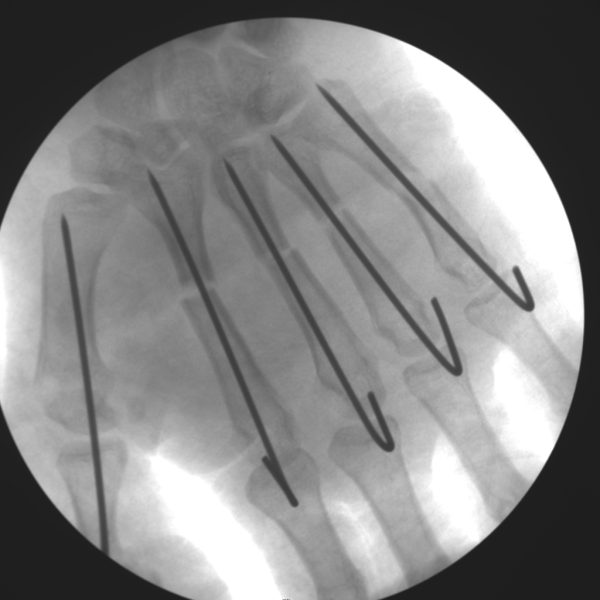

CRIF - Closed reduction internal fixation

Skan-C is a great C-arm for orthopaedic treatments for several reasons